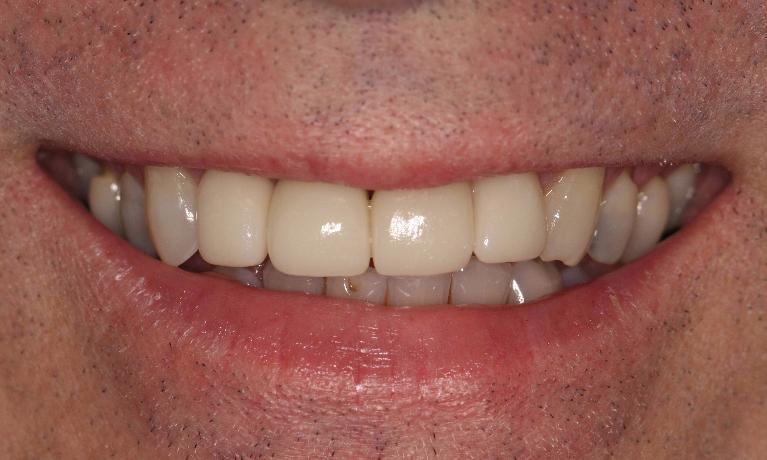

This young dad had four congenitally missing upper teeth. He had a quick orthodontic treatment and a large span bridge placed in as a teenager. He never smiles with teeth showing.

After many years of wear and tear, some of the work started to break and fail. We removed the defective bridges, managed to save all the existing teeth and placed four implant supported crowns in. The patient is very happy to be able to smile confidently now.